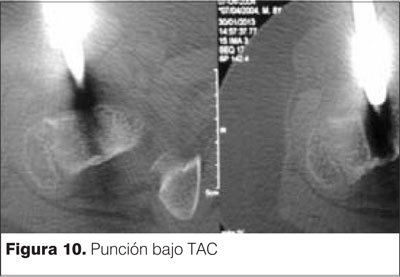

Se decide realizar procedimiento quirúrgico de resección mediante punción bajo tomografía axial computada (TAC). Se muestran las imágenes en las figuras 9, 10 y 11.

Se accede mediante un abordaje antero lateral de muslo y una punción antero posterior con trocar grueso (figura 12).

La resección en bloque bajo TAC se efectúa en sala de tomografía, en condiciones estériles, con el paciente en ayunas y bajo anestesia general(11). Utilizando cortes finos de tomografía se planifica la aproximación, logrando el trayecto más corto y seguro, libre de estructuras neurovasculares(11). Se puncionan partes blandas y corticales óseas a través del cual se introducen cánulas de calibre creciente(11). Al retirar las cánulas se obtiene material óseo, en el cual es posible reconocer fragmentos del nido(11). Este material se envía a anatomía patológica(11). Con el uso de la resección en bloque bajo TAC, se garantiza la eliminación del tumor pero se debe ser cuidadoso por el debilitamiento que se genera sobre todo en los huesos largos de los miembros inferiores y el riesgo de fracturas patológicas(11).